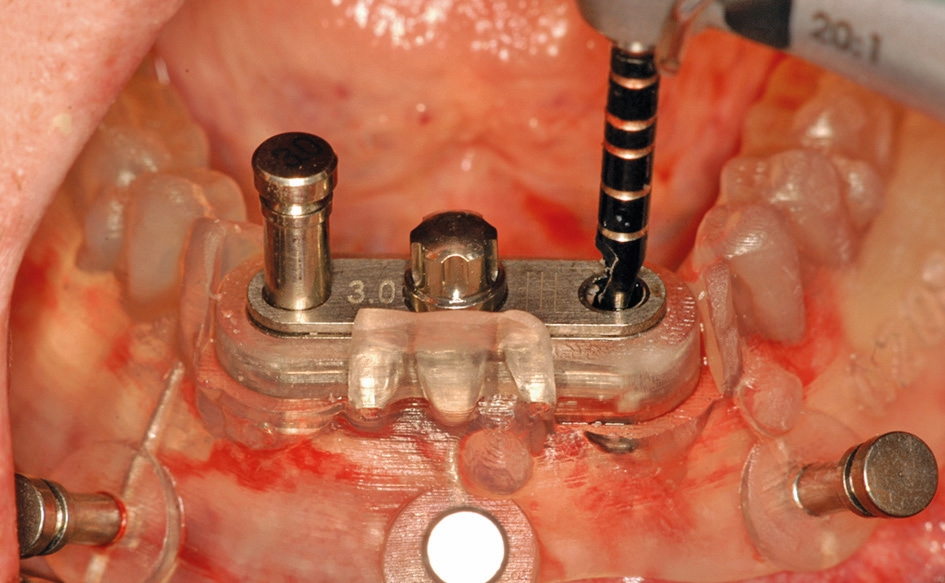

Abb. 8: Die Präparation des Implantatbettes wird durch die Doppelbohrhülse durchgeführt, die zusätzlich mit einem vertikalen Pin auf dem Kiefer stabilisiert wird.